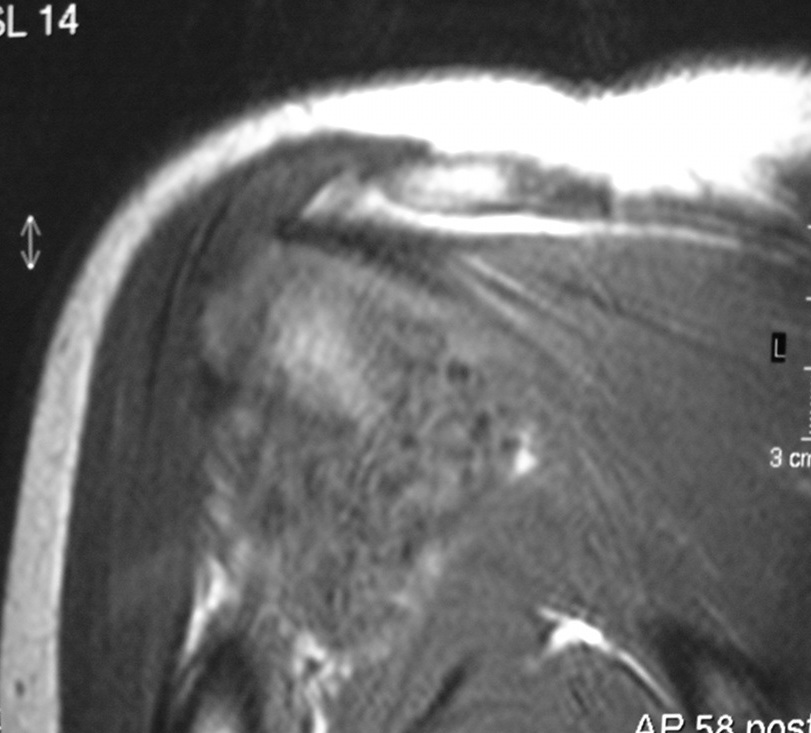

Synovial chondromatosis is an uncommon, benign, process that occurs in large joints, such as the knee (50%), hip, elbow, or shoulder. This process mainly affects synovium and hence most commonly arises from joints and tendons which are lined by synovium. Synovial Chondromatosis may also affect bursae and extend into surrounding soft tissues. This condition is seen in patients between 20 and 50 years of age and most commonly in men (male-female ratio of 2-4/1). The patient usually complains of pain, stiffness, crepitance, swelling, and joint locking. The knee is the most common site to be affected. Symptoms are long-standing and progressive. The plain x-ray may be normal (5 to 33%) or there may be small flecks of calcification (Fig. 1 & 2). On MRI the nodules of cartilage are easily seen. MR imaging may also show synovial thickening, joint erosions and intraarticular calcifications. The signal characteristics of these intraarticular bodies depend of their composition. If mineralization is not present the signal intensity follows the cartilage signal with intermediate signal on T1 images and high signal on T2 weighted MR images. Uniformly calcified bodies follows bone density on all sequences with bone marrow signal centrally and low signal peripherally (Fig. 3-5). Histologically the cartilage is arranged in nodules, which are quite cellular (Fig. 7-9). Synovial lining is present surrounding the cartilage nodules (Fig. 8). The cartilage nodules are often referred to as loose bodies however they are not really loose and embedded in the synovium lining. This is considered a metaplastic condition as opposed to a true neoplastic condition. Rarely it may turn into a malignancy usually a low grade chondrosarcoma. Malignant change is suggested by deep erosions into adjacent bone.

Fig. 4 & 5. MR images of the right shoulder. Axial (Fig. 4) and coronal (Fig. 5) T2-weighted images demonstrate high signal in the right shoulder corresponding with proliferation and swelling of the synovium. Multiple bodies with low signal that follow bone density in all sequences.